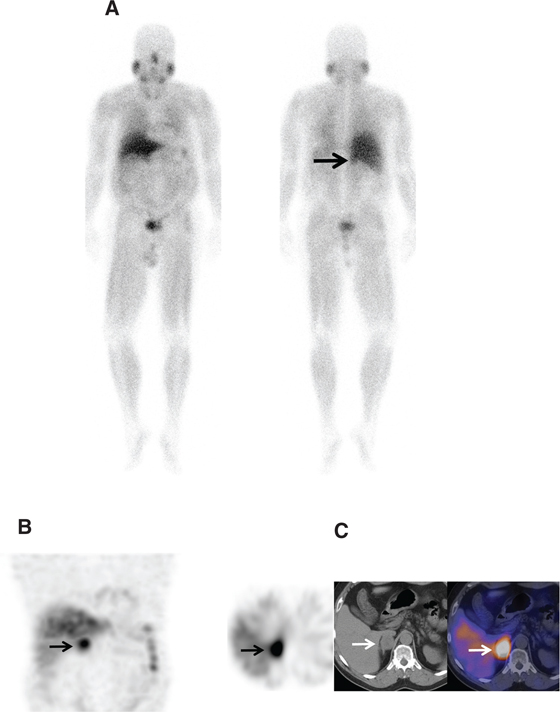

SPECT/CT improves sensitivity and specificity (Figure 6); in one case series, MIBG SPECT/CT was shown to increase diagnostic certainty in 89% of discordant CT and planar MIBG cases (41, 42).

Fig 6

Figure 6 A 40-year-old male patient with elevated catecholamines. (A) Whole body planar images, (B) coronal and axial attenuation-corrected SPECT images, and (C) axial non-enhanced CT and fused SPECT/CT images of the right adrenal region demonstrate a 4 cm × 3 cm × 4 cm soft tissue lesion with intense I-123 MIBG uptake much greater than hepatic uptake consistent with a biopsy-proven pheochromocytoma.